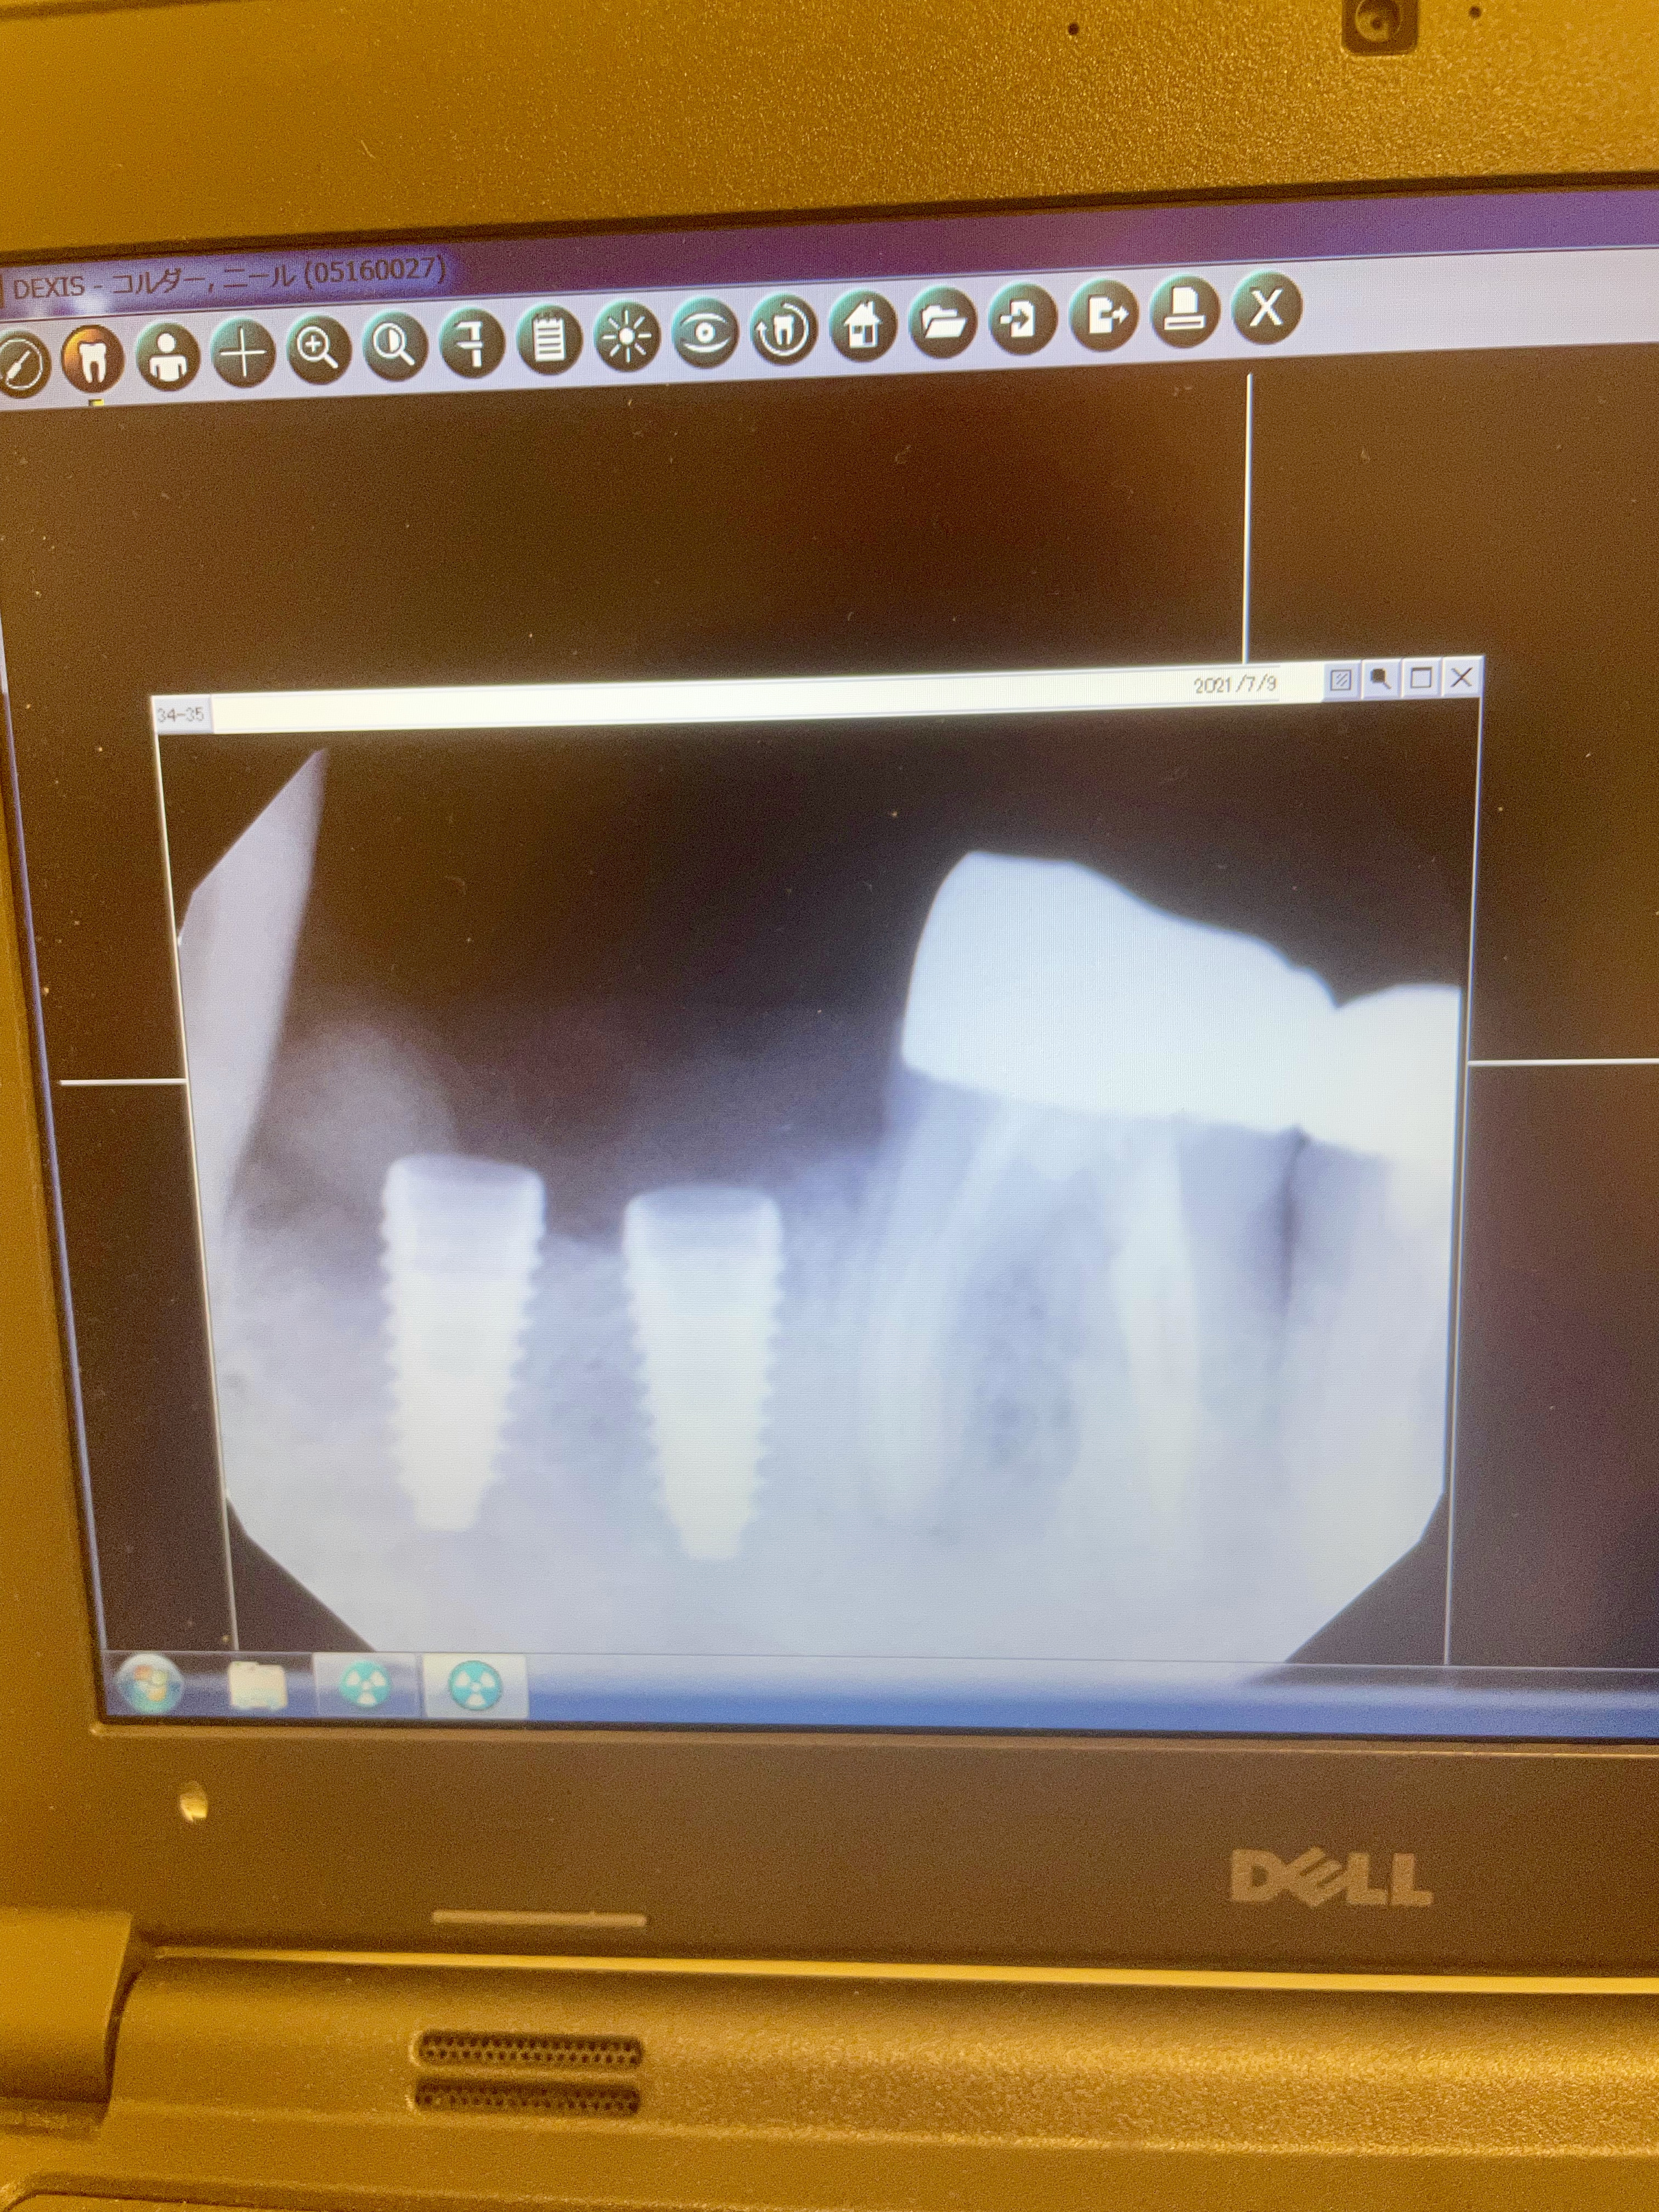

This a proper operation with surgical masks and robes. Kinjo sensei first slices through my gum, which he retracts to either side of the jaw bone. He then does all sorts of stuff until finally drilling deep holes into the jaw. I did not know what was going on at the time but he explained it to me later.

The operation took 3 hours on a scalding hot Okinawa afternoon. Not that I could see much as a surgical drape, only exposing my mouth, had been placed over my face throughout.

3 hours later it is done.